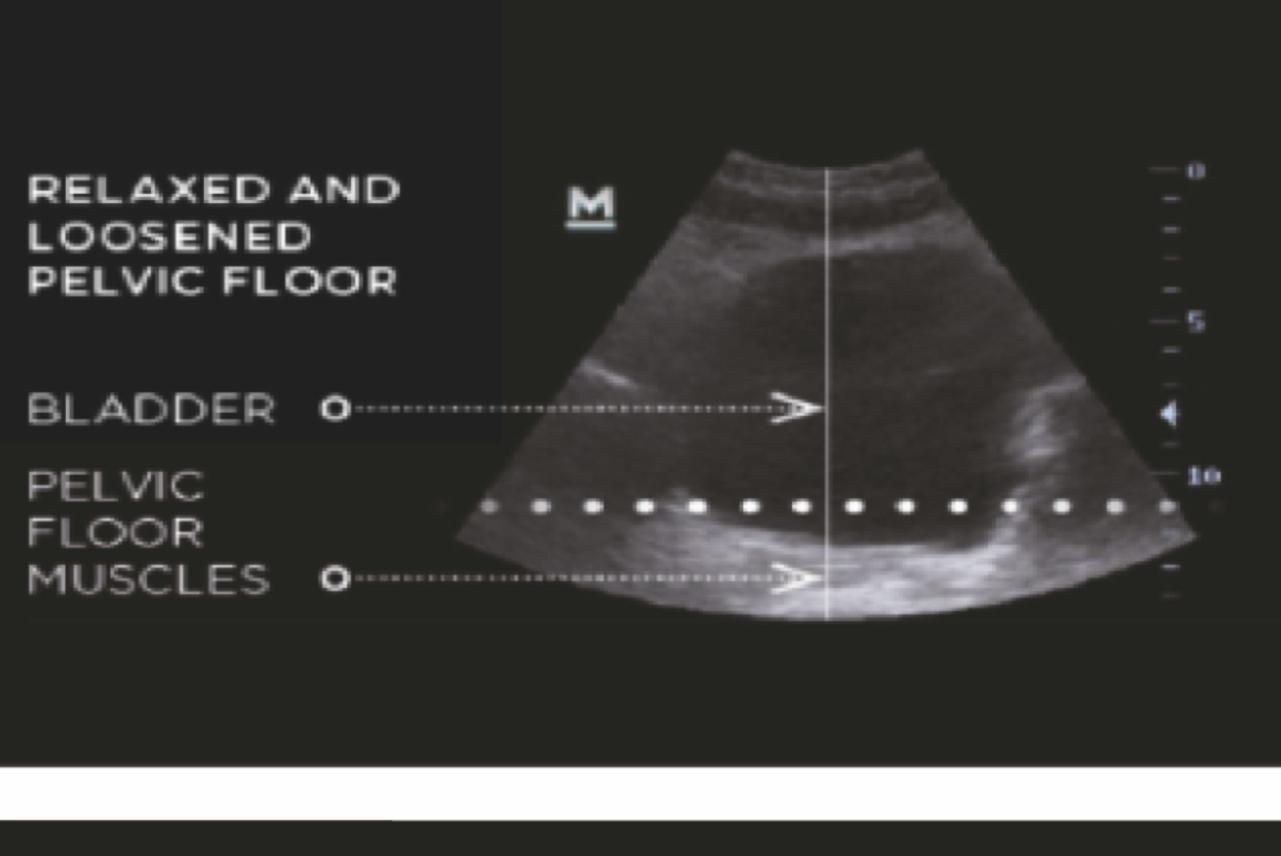

TRƯỚC

Các cơ sàn chậu không đủ khả năng hỗ trợ các cơ quan vùng chậu và ảnh hưởng đến khả năng kiểm soát bàng quang.

Bàn tập cơ sàn chậu kích thích hiệu quả các cơ sàn chậu với hàng ngàn con co thắt cơ mỗi lần điều trị.